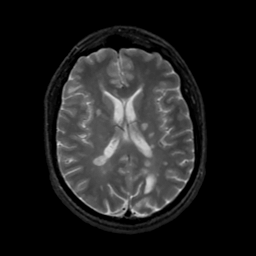

MR Study #7, March 24, 1991 -- Slice #29